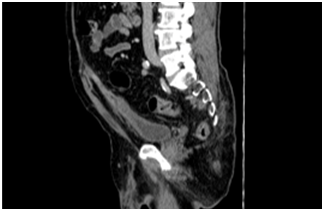

We report a case of a 72 years-old male patient who had history of previous purulent drainage through the belly bottom during the last 18 months. He had undergone to open appendectomy 14 years ago. During these episodes local treatment with topical antibiotics was performed with partial resolution. He came to the clinical office complaining about purulent discharge through the umbilicus again. CT showed a 4 cm fluid collection located in the infraumbilical middle line, communicating with the belly bottom (Figure 1 & 2). The patient accepted to undergo surgery. We performed a laparoscopic approach. Before portal placement and pneumoperitoneum we dissected the infected area inside the umbilicus, sutured with 2-0 Vycril® and left the specimen inside the abdominal cavity. Figure 3 demonstrates our standard ports placement. After this, we placed a 10 mm port, 8 cm above the belly bottom and started the pneumoperitoneum. The camera was placed in this trocar. Another two 5 mm ports were placed lateral to the rectus abdominis, one for a grasper and the other for scissor (Figure 4) Adhesions were perceived during cavity inspection.. We dissected the urachus and. a retained suture material with intense inflammatory reaction was identified (Figure 5). Bladder resection was not needed. The surgical specimen was removed through a 5 mm portal. Fascia was sutured with 0 Vycril®. Estimated blood loss was not quantified. Operative time was 94 min.Patient was discharged 24 h after the procedure and no early or late complications were reported after 60 days of follow-up. Pathology report demonstrated fibrotic connective tissue with chronic inflammation and foreign body granuloma in a 6.0 x 2.0 x 1.8 cm specimen.

Figure 1 & 2 CT sc an demonstrated images suggesting an infected urachusremnant.